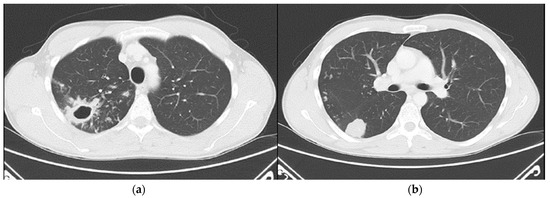

Intrathoracic lymphadenopathy was present. On 30 April 2024, the patient was transferred to the Department for Lung Diseases and Drug-Resistant Tuberculosis at Klenovnik, Varaždin General Hospital, where a shortened six-month treatment regimen (bedaquiline, pretomanid, linezolid, and moxifloxacin: BPaLM) was promptly initiated [12]. This was the first patient in Croatia diagnosed with a monoresistant form of TB resistant to rifampicin who met the criteria for the aforementioned treatment regimen. As pretomanid was not registered in Croatia at the time, it was not possible to commence the full treatment regimen immediately, in accordance with the recommended treatment algorithm. The estimated time for obtaining the drug was up to three weeks. Consequently, therapy was initially started according to the BLM protocol, including bedaquiline 100 mg (four tablets daily), which the patient received until 21 May 2024, and thereafter bedaquiline was continued at a dose of 200 mg three times per week (Mondays, Wednesdays, and Fridays). Linezolid was administered at an initial dose of 1200 mg daily for 2 weeks, followed by 600 mg daily for the next 12 weeks, and then reduced to 300 mg daily for the final 8 weeks. Moxifloxacin was given at a dose of 800 mg daily during this interim period. Pretomanid treatment was initiated on 12 June 2024, at a dose of 200 mg once daily. At that time, the moxifloxacin dose was reduced to 400 mg daily, and the patient continued therapy as per the BPaLM regimen. Throughout the entire course of therapy, regular ECG monitoring was performed, with no significant QTc interval prolongation observed. Leukocyte counts remained within normal limits, with no episodes of leukopenia. The patient did not report any locomotor symptoms, and no clinical signs of polyneuropathy were detected. Control sputum samples taken during May were AFB smear-negative, while cultures from collected sputum samples became negative in June. Subsequent sputum samples—collected monthly, two per sampling (total of nine additional samples) by the end of hospitalization—remained negative for both direct smear microscopy and culture. Chest X-rays showed complete resolution of the previously described cavity in the right upper lobe, with a persistence of soft tissue infiltrate with oval-shaped opacity in the same region (Figure 3).

Figure 3. Follow-up chest X-rays (5 June 2024) show complete resolution of the previously described cavity in the right upper lobe. However, a stable soft tissue infiltrate with oval-shaped opacity persists in the same region: (a) frontal presentation; (b) lateral presentation.